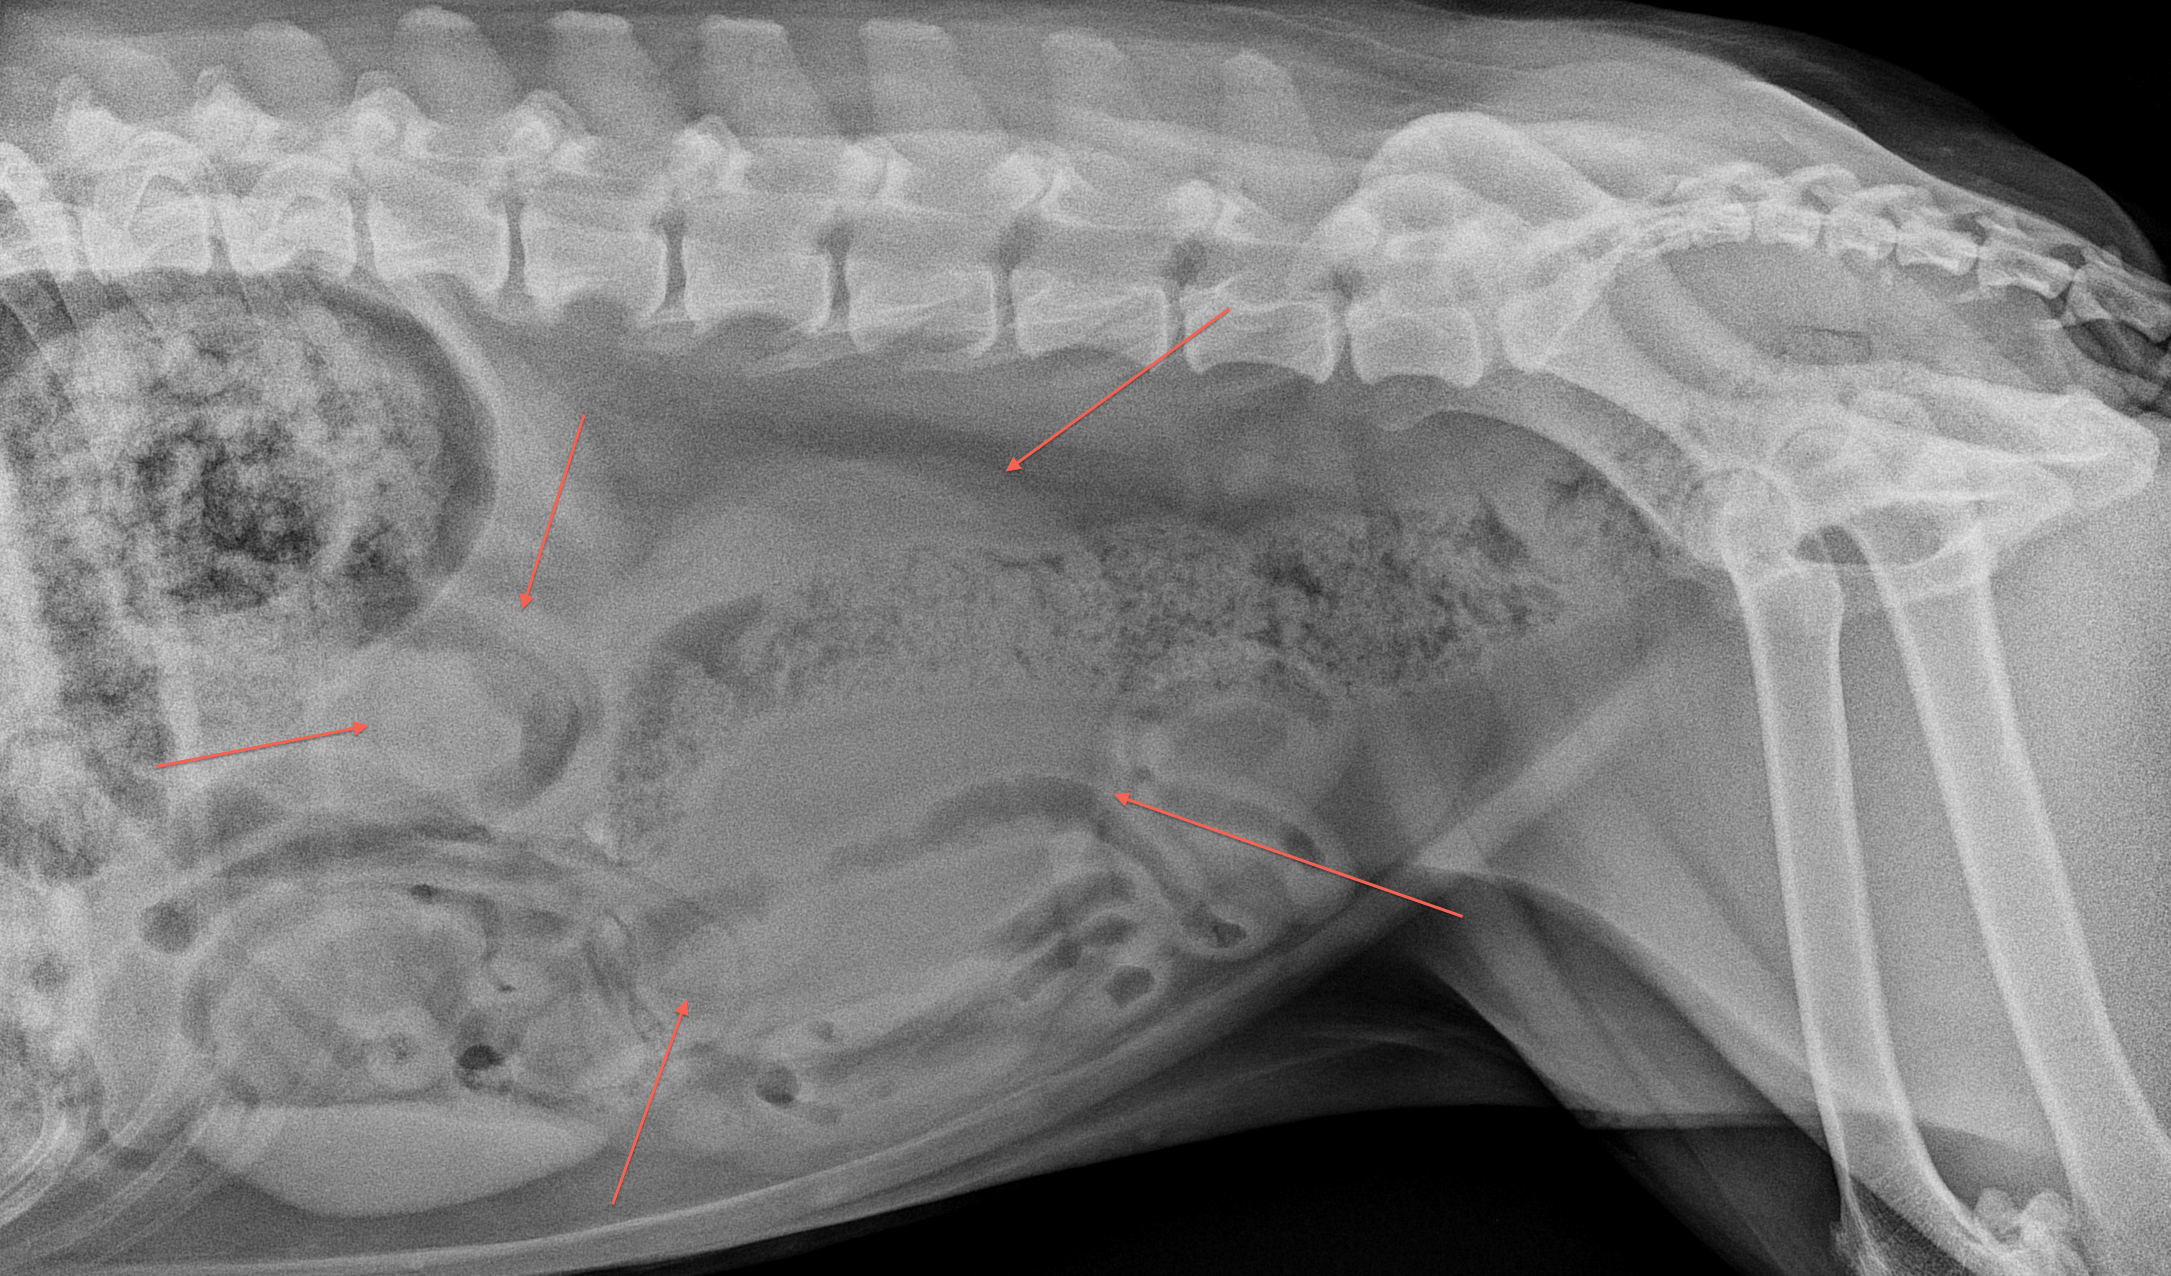

The pertinent finding on this case is the presence of an abdominal mass which is located in the mid-dorsal abdomen to the left of midline, displacing the bowel ventrally and to the right side. Careful inspection shows no evidence of a normal left renal silhouette, so unilateral renomegaly has to be the top differential. The irregular shape makes obstruction / hydronephrosis less likely, so the most likely causes renomegaly would include neoplasia or a large renal cyst.

Annotated Lateral